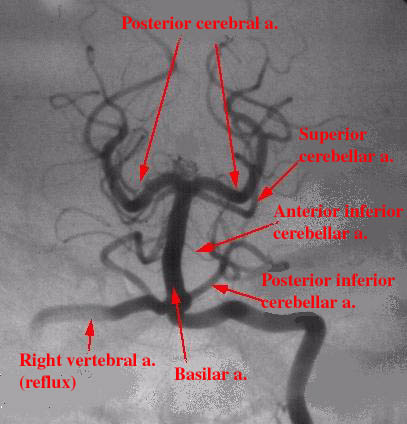

Angiography of the posterior cerebral circulation showing vascular

supply of the brain stem.